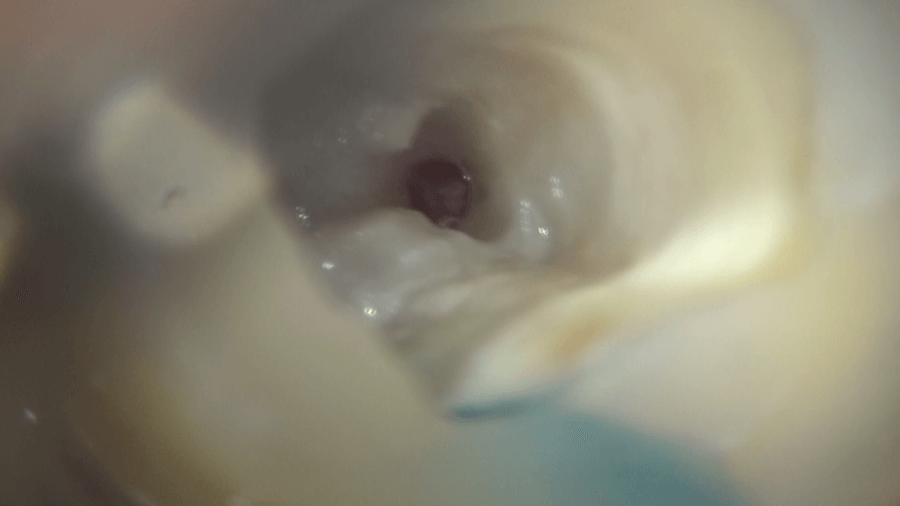

まず、歯に穴を開けます。

内部にあるゼリー状の組織、歯髄が見えます。これがいわゆる神経です。

もう少し大きくすると、内部に石のようなものが確認できます。

触ると動きます。

上部の歯髄を溶かすと、4つの根管の入り口が見えます。